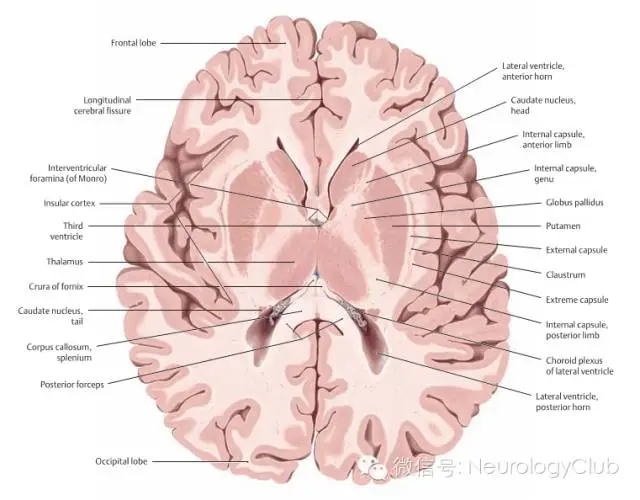

(图4:基底节区解剖示意图。引自:Head and Neuroanatomy.Thieme Medical Publishers Inc;1st ed. 2010)